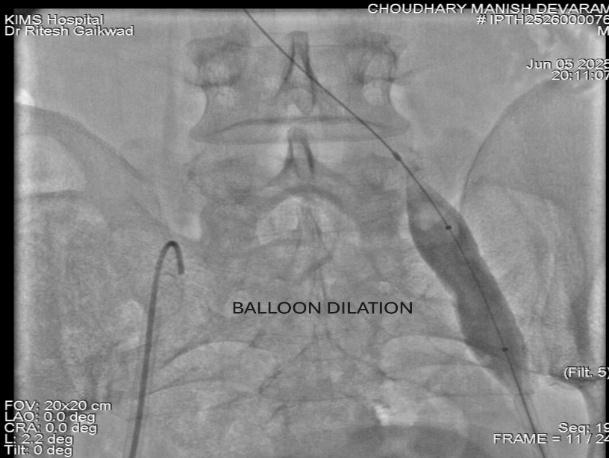

The patient underwent balloon angioplasty followed by deployment of a dedicated self-expanding venous stent in the compressed segment of the left iliac vein. The procedure was uneventful, completed in under an hour, and the patient was mobilized within two hours postoperatively.